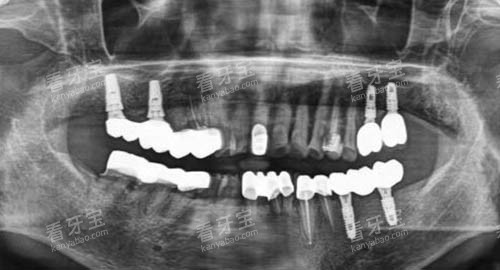

在设备方面,大连马泷齿科紧跟国内外头部技术,配备了一系列可靠的口腔诊疗设备。

例如,口腔CT设备能够提供高精度的口腔内部影像,帮助医生更更准地诊断病情;智能化正畸设备则可以实现个性化的正畸方案设计,大大提高了正畸治疗的结果和效率。

这些可靠的设备为高质量的口腔诊疗服务提供了坚实的硬件基础。

例如,在牙齿种植方面,医生会在术前对患者进行齐全的口腔检查和评估,制定科学合理的种植方案,采用可靠的种植技术和优质的种植材料,确保种植手术的成功几率和安心性。